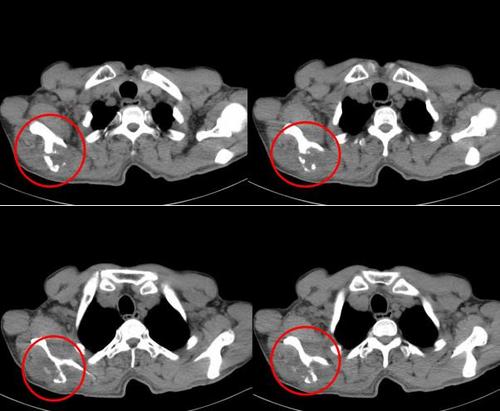

一位男性患者前列腺癌手术后2年多,疾病控制得很好,没有复发迹象。一天,他突然出现会阴部疼痛,入院检查发现骶骨及尾骨转移,于是患者接受了骨转移的姑息性放射治疗,还进行了双磷酸盐的骨修复治疗,局部未再出现疼痛。

1年后,对侧坐骨又出现了疼痛,“有经验”的患者直接来到了医院放疗科就诊,经过医生仔细地检查评估以后,上次放射治疗过的病灶已经部分愈合,这次疼痛的部位出现了新的病灶,但仍然局限。于是,放疗科医生仔细地给他设计了放疗方案,既保证了新病灶的治疗,又确保曾经接受过治疗的周边正常组织不会超出耐受剂量量引起不良作用。2周以后,疼痛缓解。患者再去接受了新一轮的内分泌治疗,不用挨痛,回家休养了。

有些转移病灶需要进行手术治疗,比如承重的骨骼(下肢、脊柱),如果病变已经累及50%以上,或股骨颈的病变大于2.5cm,容易发生病理性骨折,预计生命大于6周则应该先进行内固定治疗。